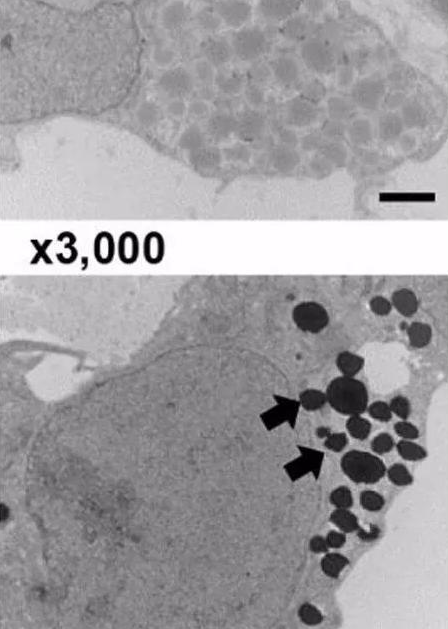

120.png

圖. 電鏡下細(xì)胞內(nèi)EPO的分泌囊泡